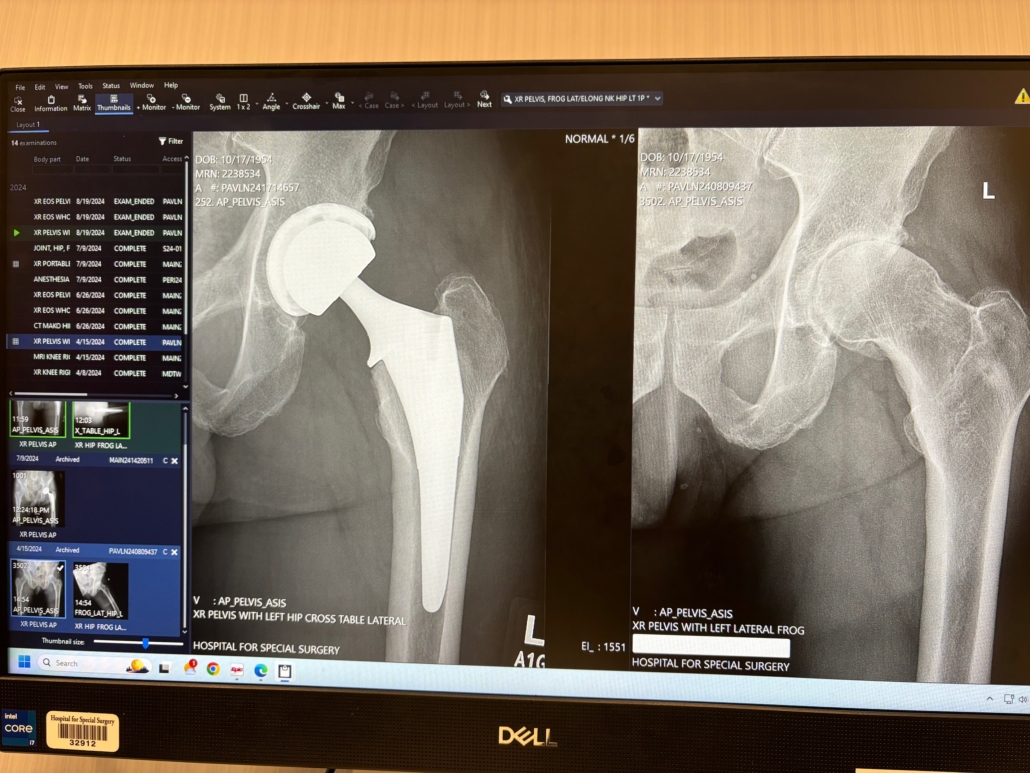

X-Ray of John Gleb’s Hip

Three months later, in early July, I had the surgical procedure done in New York City.